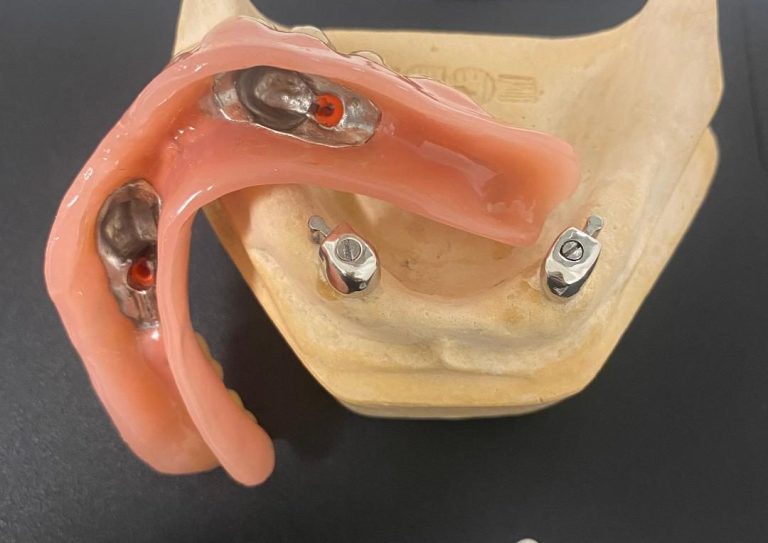

Implantat Magnet Prothese (Magnetics)

Magnetics: ist das Zauberwort für modernen Implantat Zahnersatz im Bereich Total- und Teilprothetik.

Das ständige Auswechseln von Einsätzen, so wie bei den meisten anderen Systemen entfällt!

Die Eingliederung der Prothese ist vereinfacht. Die Prothese findet von allein in die richtige Position.

Implantat basiert getragene Magnetprothese (als Alternative z.B. für Locator©, Kugelkopfanker etc.)

Bei unserer UK Magnetprothesen Schauarbeit sind 2 in Regio 33,43 und 2 in Regio 36,46 verbaute Magnet Implantat Abutments, mit einer Abzugskraft von 1,2Kg pro Kiefer.

Bei unserer OK Magnetprothesen Arbeit handelt es sich um eine eingegliederte Patienten Arbeit mit 2 in Regio 13,24 und 2 in Regio 16,26 verbaute Magnet Implantat Abutments, ebenfalls mit einer gewünschten stärkeren Abzugskraft von 1,2 Kg pro Kiefer.

(Norm sind 700g Abzugskraft).

Diese Arbeit wurde für den 82 jährigen Patienten auf Wunsch Gaumenfrei gestaltet. Trotz Parkinson Erkrankung kam der Patient

sofort mit der Ein- und Ausgliederung dankbar und prima zurecht.